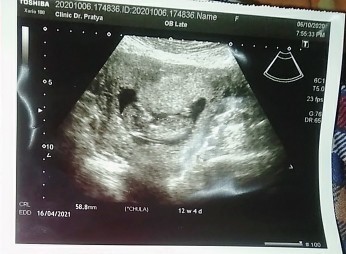

แบบนี้น้องกี่วีค ยึดตัวไหนเป็นหลัก😥 ถามคุณหมอ คุณหมอบอก 11 วีค

11วีค4วันจ้า

11w4d